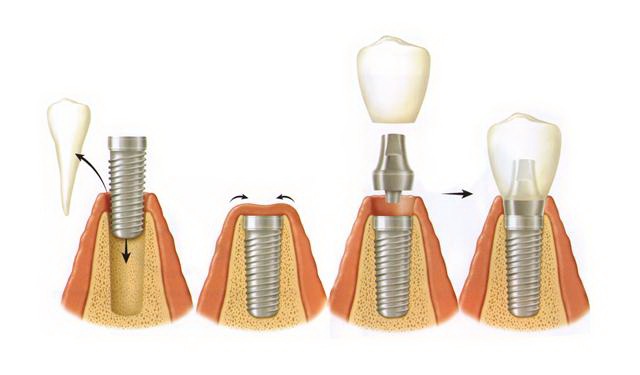

Все манипуляции состоят из 3-х этапов:

1) хирургический;

2) промежуточный;

3) ортопедический.

Хирургический этап

Для выполнения дентальной имплантации производится местная анестезия. Делается разрез десны в области отсутствующего зуба, отодвигается десна. В костной ткани препарируется ложе для имплантата, затем устанавливается имплантат с необходимым усилием. В имплантат устанавливается заглушка, затем накладываются швы. После операции выполняется контрольная рентгенограмма.Вся операция при стандартных условиях занимает не более 30-40 минут.

Промежуточный этап

После установки имплантата через 3-6 месяцев, в зависимости от верхней или нижней челюсти, на имплантат под анестезией устанавливается формирователь десны для формирования будущего десневого края под постоянную коронку.

Ортопедический этап

Через 3 недели после установки формирователя десны пациент приходит на приём к стоматологу-ортопеду для снятия оттисков и изготовления коронки на имплантат.